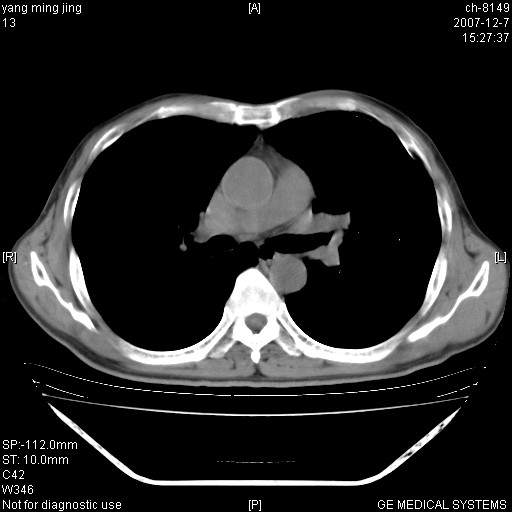

以下是引用zsl6918在2007-12-7 22:22:00的发言:[br]左肺上叶中心性肺癌并肺内及纵隔淋巴结转移,肝内转移。小细胞肺癌可能性大。

以下是引用狙击手在2007-12-8 11:03:00的发言:[br]考虑:左肺上叶中心性肺癌并肺内及纵隔淋巴结转移,肝内转移。